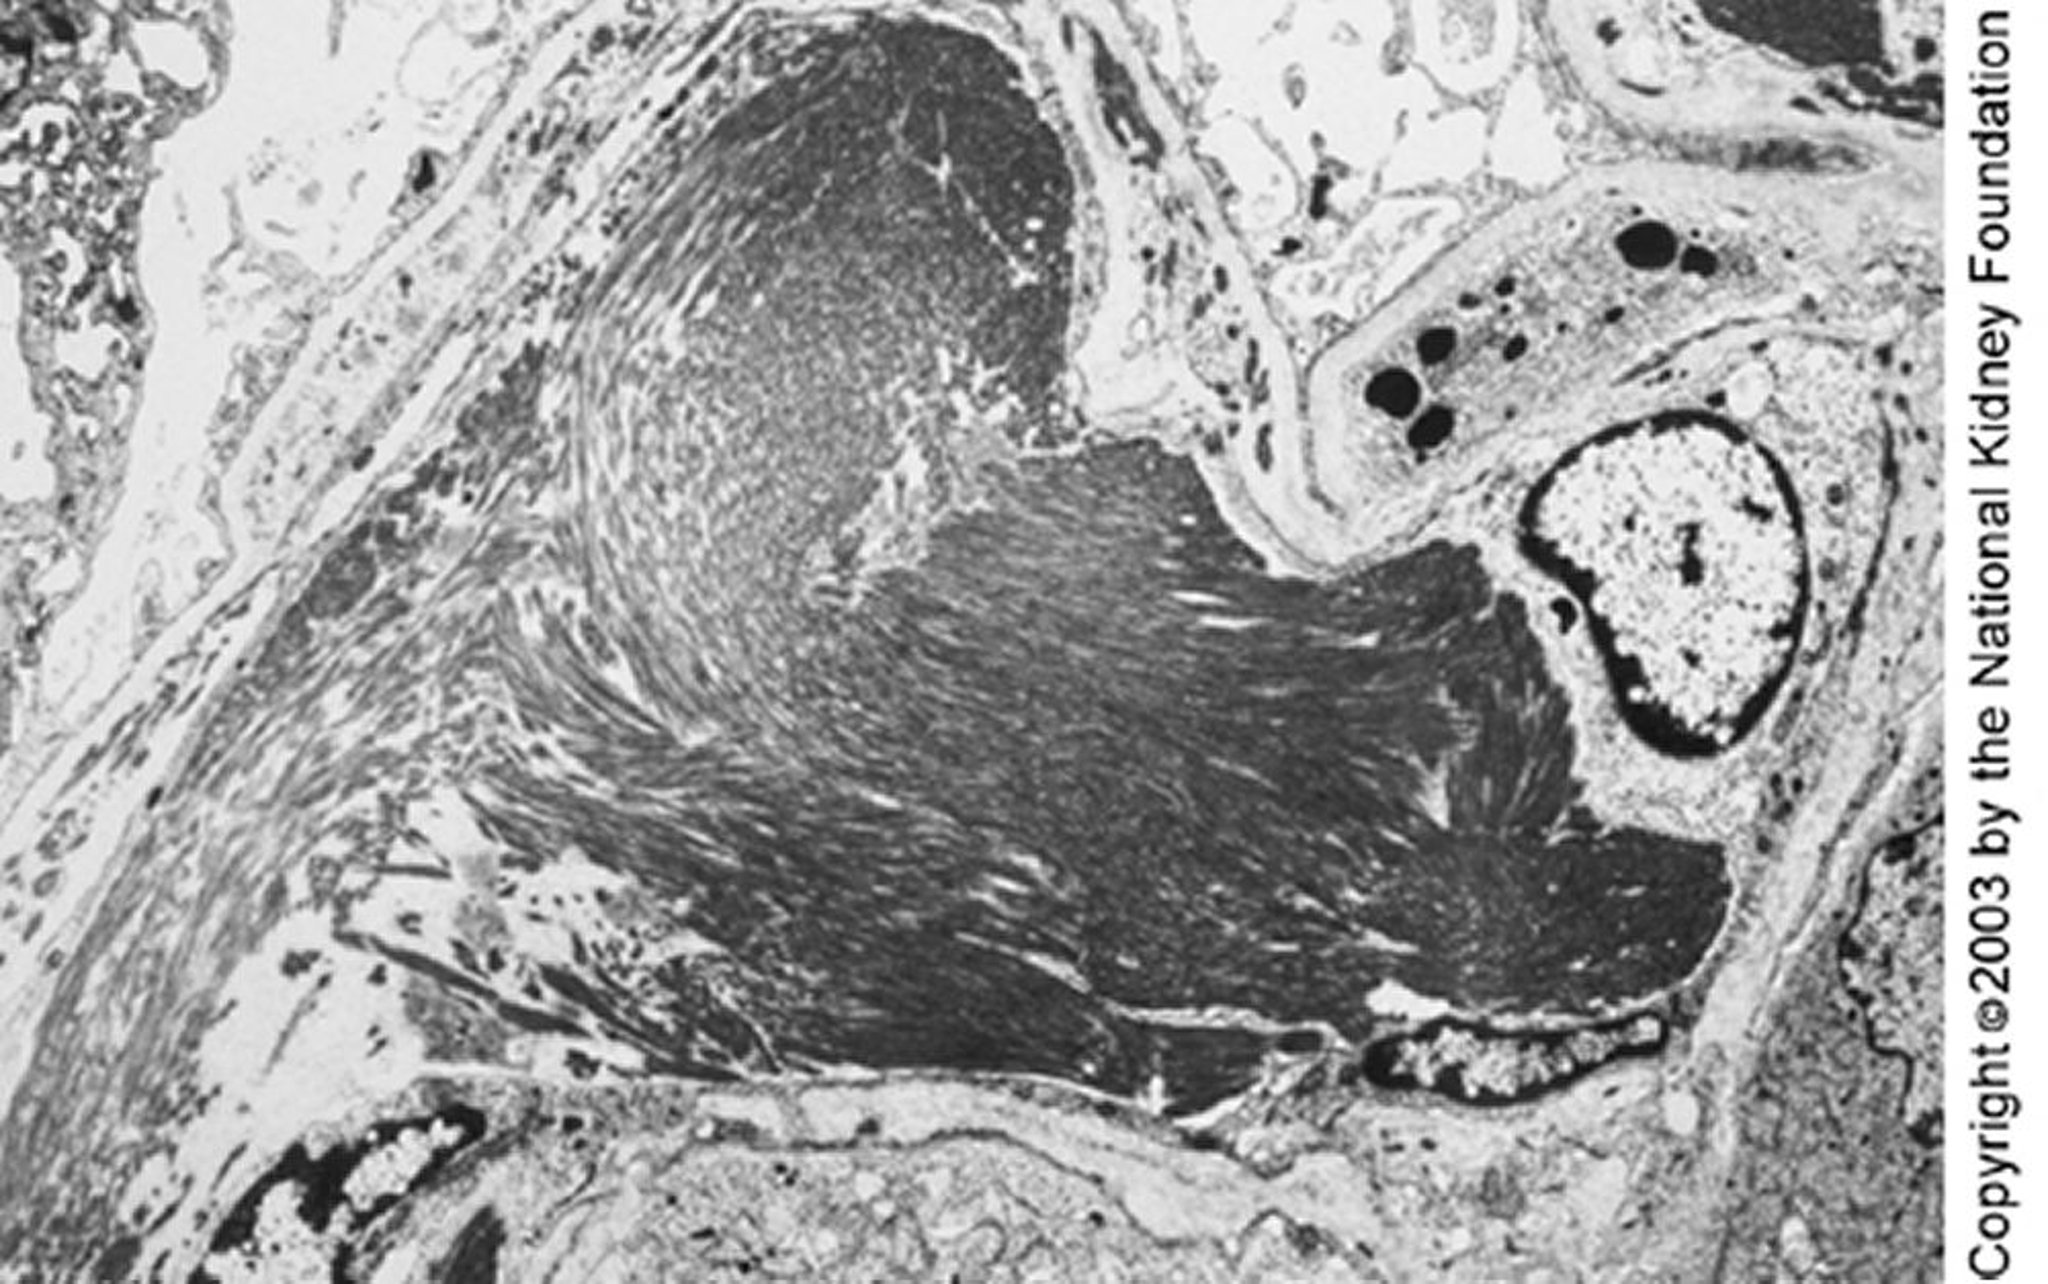

Glomerulopatia immunotattoide

Grandi microtubuli (circa 50 nm di diametro) organizzati in matrici parallele possono essere visti alla microscopia elettronica a trasmissione. I depositi paralleli e la struttura microtubulare possono permettere di distinguere la glomerulopatia immunotattoide da quella fibrillare (×4000).

Imagine fornita da Agnes Fogo, MD, and the American Journal of Kidney Diseases' Atlas of Renal Pathology (vedi www.ajkd.org).